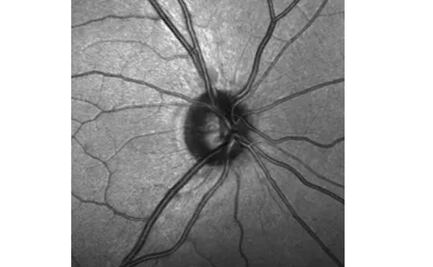

Descubren células madre en el nervio óptico

Sin estas células, el nervio es incapaz de repararse a sí mismo de los daños causados por el glaucoma